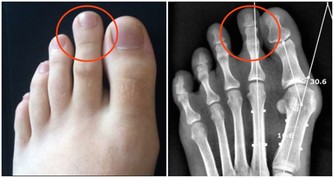

放屁太臭不只是尷尬的事

公共場合一個臭屁,著實令人尷尬,臭屁大多是由於於腸道內有較多的糞便滯留沒有及時排出,在腸道內聚集而成。